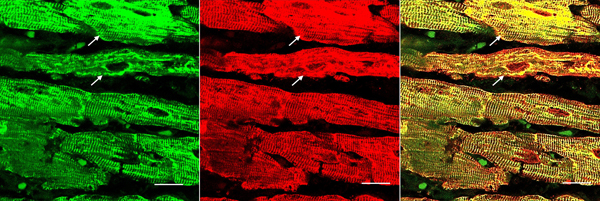

Double-label laser scanning confocal immunofluorescence: Figure 6 shows the colocalization of desmin and αB-crystallin in Z-discs and intercalated discs. In FA, intercalated discs are wider at approximately 50 µm than normal (approximately 23 µm) and have undergone chaotic disorganization (fig. 6d). A more advanced fiber destruction is illustrated in figure 7. Two adjacent fibers display accumulation of desmin and αB-crystallin, obliterating the contractile apparatus of the cardiomyocytes. A search for amyloid by polarizing light for apple-green birefringence and Congo Red fluorescence did not reveal amyloid deposits. Figure 8 shows double-label immunofluorescence of desmin and ATP5B. All fibers in FA contain clusters of mitochondria, visualized by green fluorescence of ATP5B, and one cluster is surrounded by a rim of desmin. In normal cardiomyocytes, mitochondria occur in rows of delicate granules between heart fibrils (fig. 8, top row).

Figure 6. Double-label laser scanning confocal immunofluorescence microscopy of desmin and αB-crystallin. Desmin immunofluorescence (a, d) is Alexa Fluor 488 green, αB-crystallin (b,e) Cy3 red. Merged images appear in c and f. The top panel (a-c) represents a normal control, the bottom panel (d-f) FA (man, 24, GAA 700/1050). Desmin and αB-crystallin fluorescence colocalize at intercalated discs (arrows) and Z discs. In FA, an intercalated disc has undergone chaotic modification. Bars, 10 µm.

Figure 7. Desmin and αB-crystallin overload in FA cardiomyopathy (same patient as in fig. 6). Desmin is shown as Alexa Fluor 488 green, αB-crystallin as Cy3 red, The merged image on the right shows extensive colocalization of these protein and destructive aggregation in two fibers (arrows). Bars, 10 μm.

Figure 8. Double-label laser scanning confocal immunofluorescence microscopy of desmin and ATP5B. Top row, normal control; bottom row, FA (same patient as in fig. 5). Desmin is shown as Cy3 red, ATP5B as Alexa Fluor 488 green. In the normal control, mitochondria appear as rows of punctate green organelles aligned along fibrils. In FA, green mitochondria appear in clusters (arrows). The upper cluster is surrounded by a desmin deposit. Bars, 20 µm.